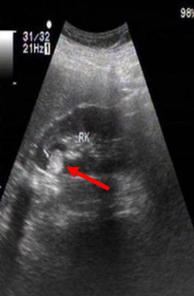

诊断通常依赖B超和CT或MRI:B超下表现为高回声结节,当然偶尔会有混合回声。CT通常显示肿瘤内部有极低密度值的脂肪成分。部分乏脂性错构瘤诊断较为困难,需依靠病例确诊。

B超下典型表现为 高回声结节